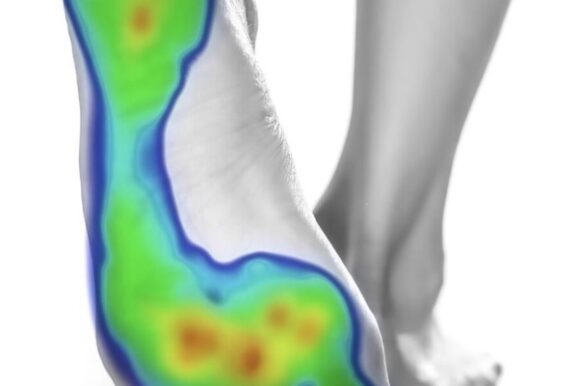

Beneficios del estudio de la pisada Prevención de lesiones y…

Todos y cada uno de los tratamientos que ofrecemos los enfocamos desde un punto de vista podológico y multidisciplinar, en caso de necesidad. Gracias a nuestro amplio conocimiento en biomecanica del pie, abordamos la patología podologica o corporal asociada con la premisa de respetar el correcto funcionamiento del aparato locomotor durante la deambulación, actividades cotidianas, deportivas e incluso laborales.

Un tratamiento a medida Las ortesis plantares no solo son…